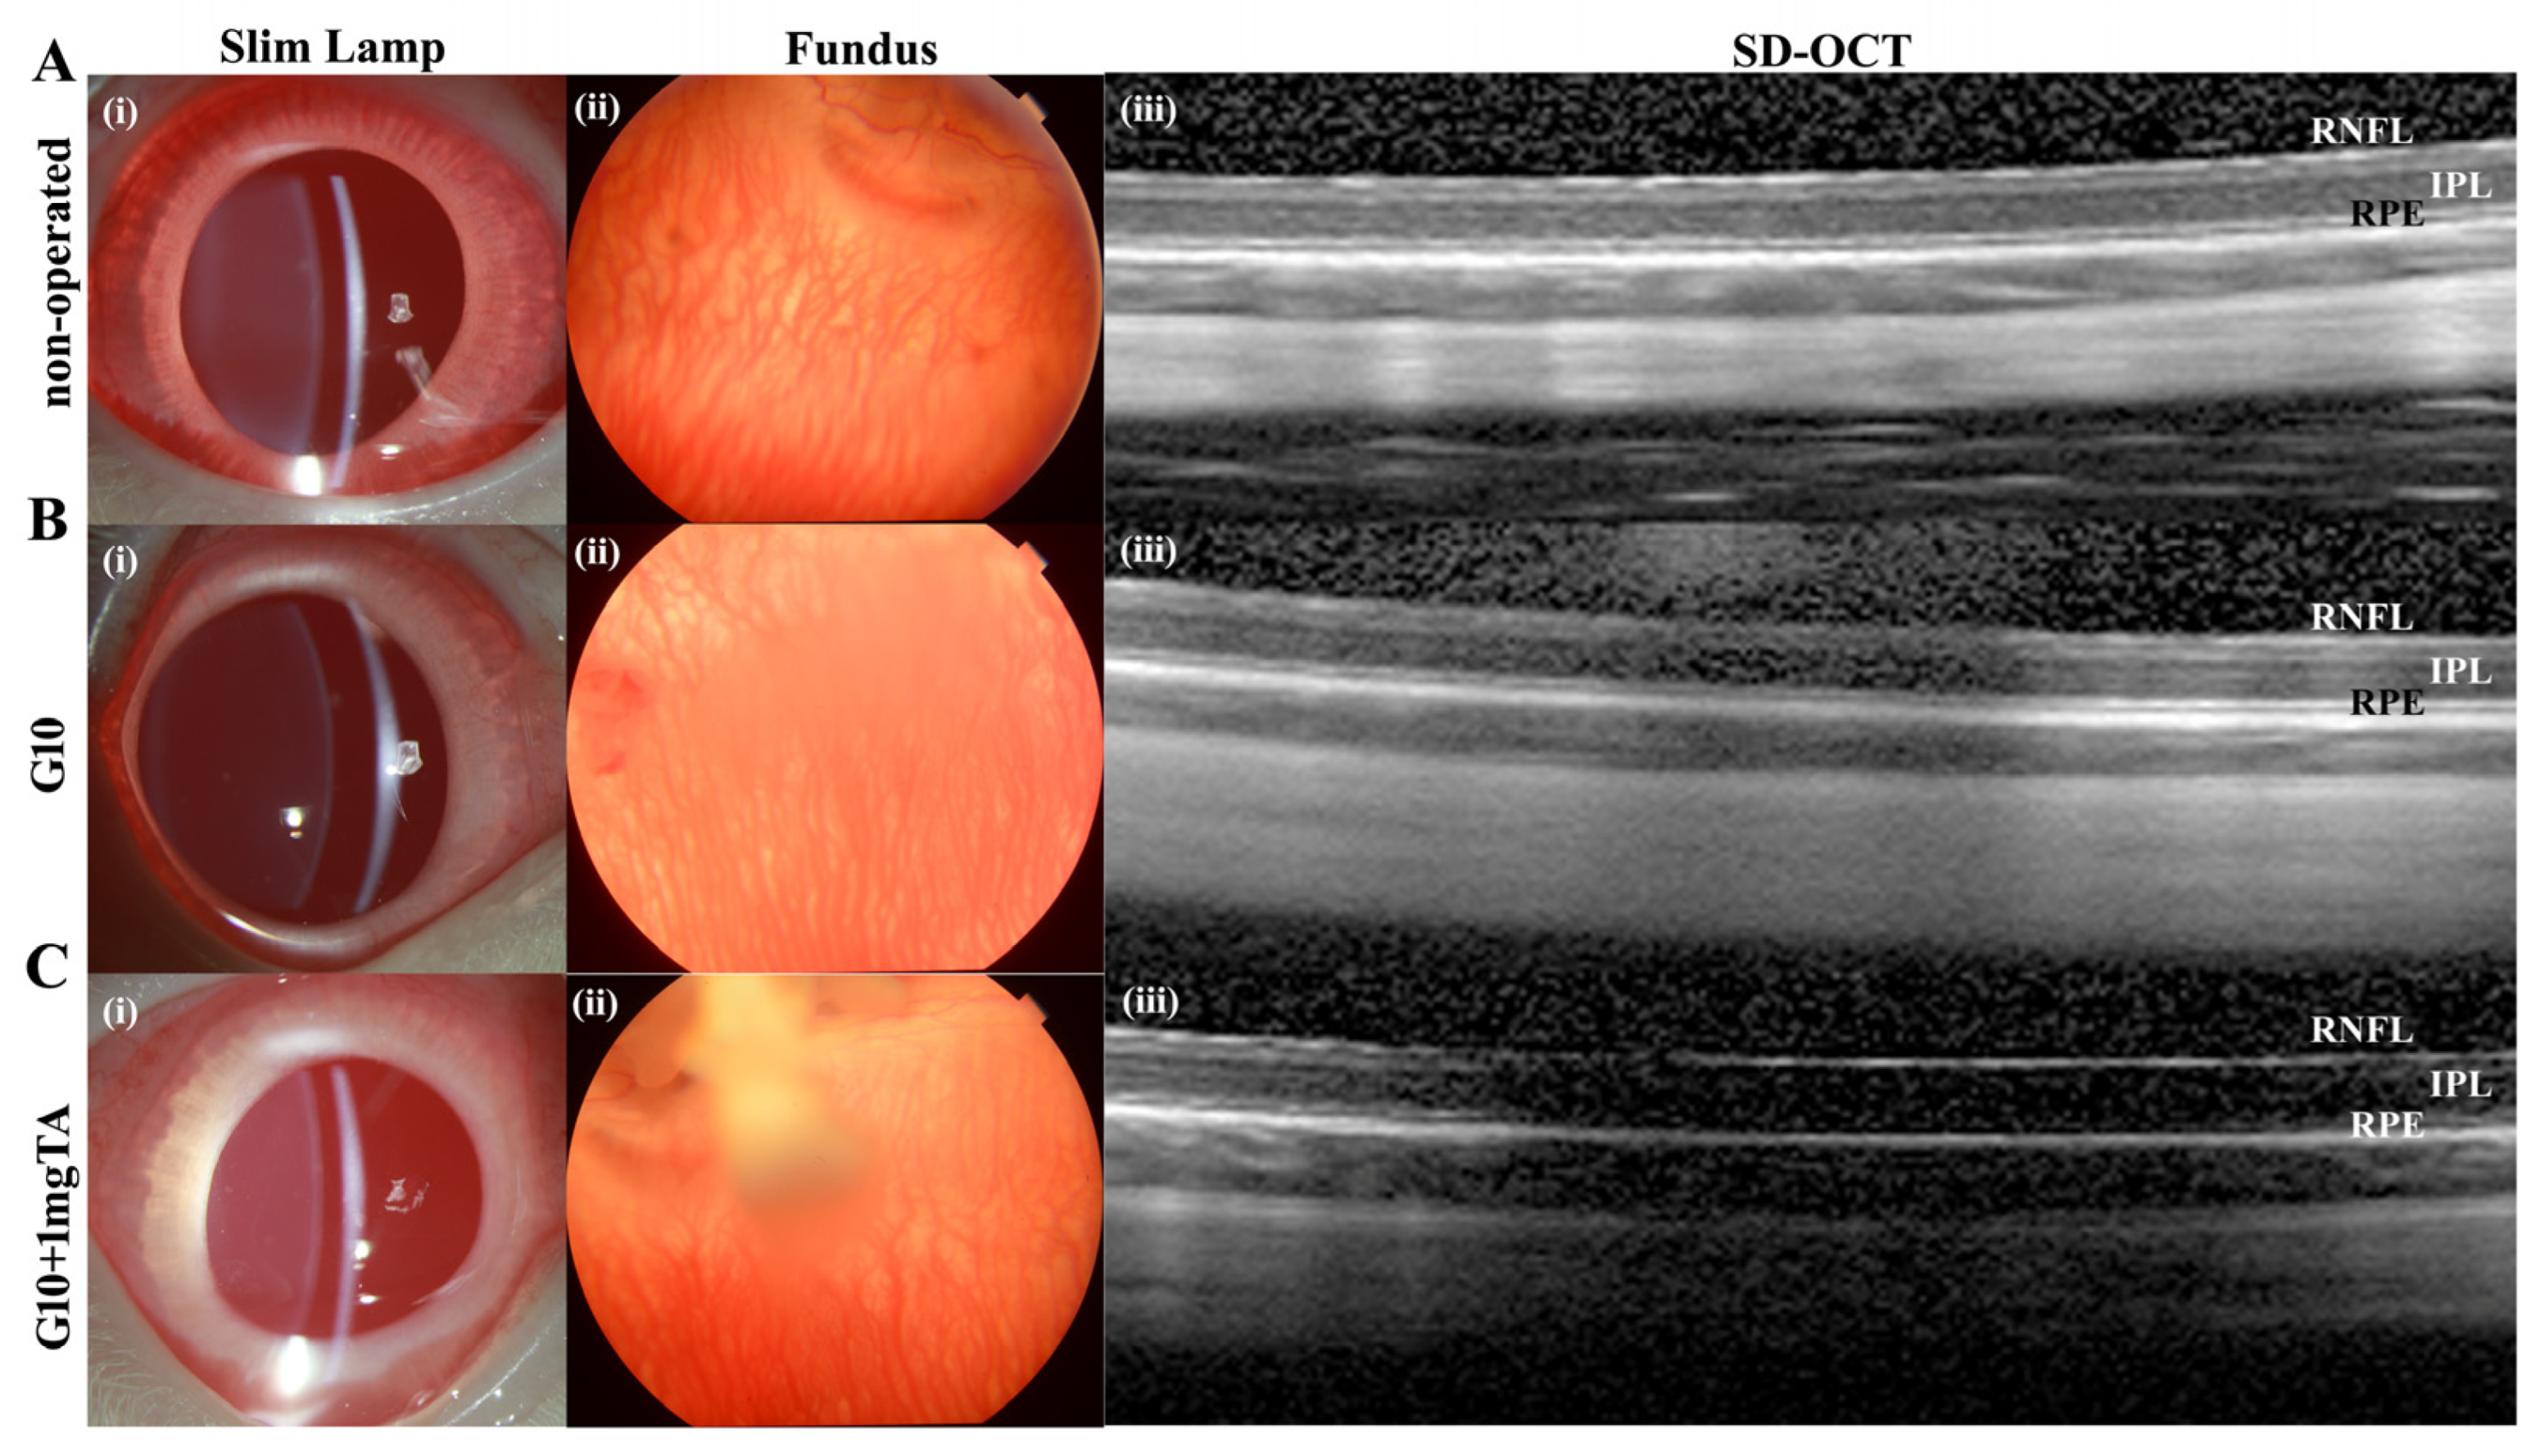

Figure 6.

In vivo imaging and ex vivo retinal analysis of rabbits 7 d after implantation of GelMA hydrogels. (A–C), Column (i): slit-lamp images of operated BSS controls and G10- and G10 + 1 mg TA-injected eyes, showing no significant inflammation or cataract formation. Column (ii): images of the fundus showing normal appearance of the optic disc and normal vessel morphology in all groups. Column (iii): SD-OCT images obtained in all four groups revealed no reduction in retinal thickness from the RPE to the RNFL.